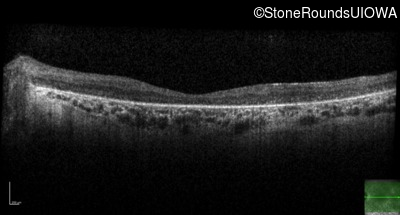

Optical Coherence Tomography - Right - 10/140 sc

Exemplar / OCT Stack